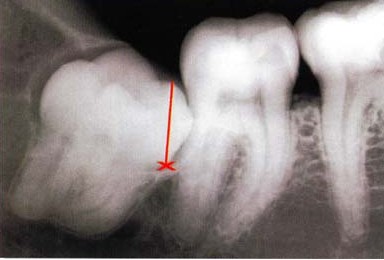

4、侵犯邻牙。通常患者不自知,而由牙医以X光诊断得知。智齿萌发的空间不足,倒在第二大臼齿上,因而造成第二大臼齿清洁不易,甚至是牙齿部分吸收的现象,造成患者不舒适或牙疼。